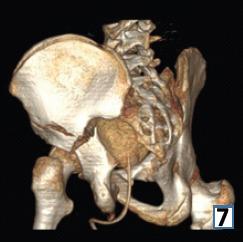

在此,我们报告一例16岁男性,有道路交通事故史,单纯闭合性左髋臼骨折。X线显示双侧髋臼柱骨折伴中心性半脱位。通过改良的Stoppa入路并带有外侧窗口对其进行切开复位内固定治疗。患者在受伤后第6天接受了ORIF。使用钢板和螺钉进行固定。在恢复室,他整个左上肢无法活动且无感觉,而手术肢体的远端神经血管功能正常。恢复15分钟后,感觉恢复,但运动功能障碍持续存在,提示臂丛神经失用。进行了脑部CT扫描,结果未见异常。6个月后,患者自行恢复了感觉,左上肢力量改善至5/5。

https://cdn.ncbi.nlm.nih.gov/pmc/blobs/99f1/12064220/4b0a3e1fbd1f/JOCR-15-43-g007.jpg